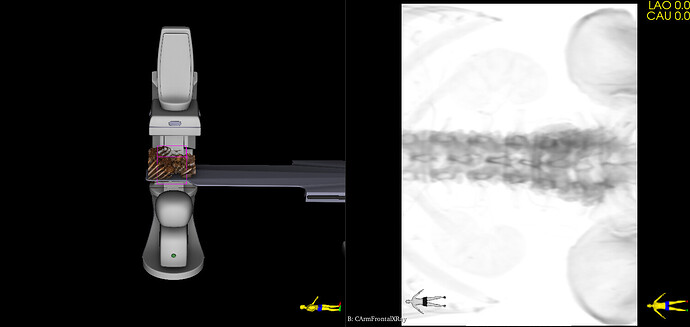

Virtual Cath Lab module has been recently added to SlicerHeart extension. This module simulates monoplane and biplane C-arm systems: provides 3D model of the C-arm, table, patient and generates simulated fluoroscopy images. Images can be either static (generated from 3D CT) or dynamic (generated from 4DCT). The module can also display cardiac devices (stents, occluders, clips, etc. provided by the Cardiac Device Simulator module) and virtual contrast filling (from image segmentation).

The module was developed for cardiac and vascular procedures, but it is well suited for simulation of any fluoroscopy guided procedures.

However, the default position of the C-arm in the vascular context is not always at the head of the patient (rarely actually), it is rather perpendicular to the table. The L-arm angle slider can do that but the orientation of the DRR is then rotated accordingly.

Would it be possible to optionally have a default position of the C-arm perpendicular to the table, on its right or on its left, with an upright DRR?

I’ve updated the module with the followings:

• Added detector rotation angle (no auto-rotation is available, but the rotation can be easily manually adjusted on the GUI)

• Default L arm angle is set the C-arm to be at the side of the table

• Projection beam is displayed (to make it easier to see the field of view in 3D)

• Detector size is configurable in the preset .csv files